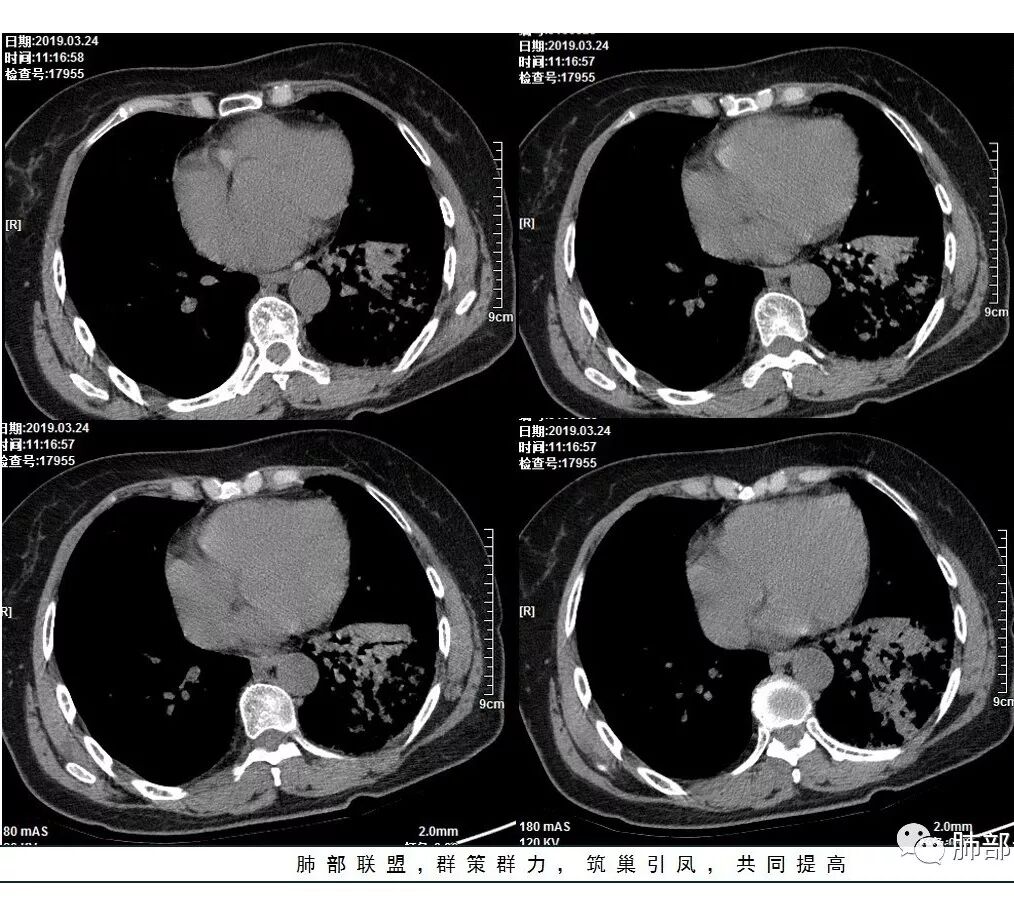

1、主病灶  左下叶斑片状、大片状致密影

2、两肺马赛克灌注

3、两侧肺门区钙化淋巴结

总共就这三大块

这三幅图是连续的,我们看到支气管中间这一幅狭窄了

大——小——大,狭窄后扩张

从这幅图看好像与周围病灶分界不清,支气管腔狭窄后扩张,支持炎性

两肺门钙化淋巴结一般考虑:结核?尘肺?淀粉样变性?

这是老问题:1、肺门区软组织密度影较弥漫;我们常规鉴别的就是结核?鳞癌?既往我们群里基本这两方向。2、弥漫的淋巴结钙化,加上马赛克灌注。马赛克灌注的原因是两个,一个是肺动脉的,一个就是小气道的问题。我们看增强的区域,没有看到栓塞,所以我倾向于小气道的问题,就是弥漫气道病变,慢性气道病变要考虑。我怀疑有没有淀粉样变性累及气道壁改变的可能。淀粉样变性是一个继发性病变,结核也可以,粉尘也可以。

这个病例支气管狭窄后扩张,肺门区有很多钙化的淋巴结,两肺弥漫的马赛克灌注,肺门淋巴结这么多,一个结核,一个尘肺,然后就是一个淀粉样变性,这几种最常见。鳞癌因为老年女性,除非吸烟,不太考虑,又不能绝对排除,所以就把鳞癌放到后。